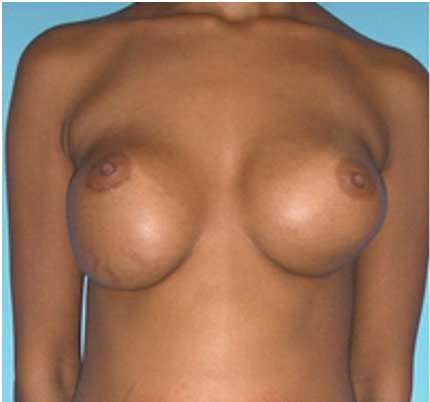

This patient presented to Dr. Agha for breast augmentation.

The patient had subtle breast asymmetry, with the right breast being smaller and than the left. This was appropriately corrected with the use of different-sized implants.